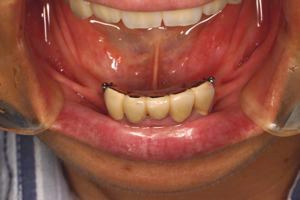

インプラント義歯 ミニインプラント症例

術前術前主訴-総入れ歯の安定が悪い 即時加重可能のミニインプラント使用した。 術前レントゲン術前レントゲン術前レントゲン CT撮影から3次元骨モデルを作成CT撮影から3次元骨モデルを作成CT撮影から3次元骨モデルを作成し埋入位置の確認 フィクスチャーを浸潤麻酔下で埋入フィクスチャーを浸潤麻酔下で埋入。歯茎を切らないので患者さんも非常に楽

4本埋入終了4本埋入終了4本埋入終了(このシステムは4本が絶対条件) 義歯の調整義歯の調整当日に義歯の調整に取りかかる。裏側より義歯をくりぬき維持部のカバー(ハウジング)を義歯の内面に埋め込む step1 義歯の調整義歯の調整当日に義歯の調整に取りかかる。裏側より義歯をくりぬき維持部のカバー(ハウジング)を義歯の内面に埋め込む step2 義歯の調整当日に義歯の調整に取りかかる。裏側より義歯をくりぬき維持部のカバー(ハウジング)を義歯の内面に埋め込む step3

義歯の調整義歯の調整当日に義歯の調整に取りかかる。裏側より義歯をくりぬき維持部のカバー(ハウジング)を義歯の内面に埋め込む step4 義歯の調整義歯の調整当日に義歯の調整に取りかかる。裏側より義歯をくりぬき維持部のカバー(ハウジング)を義歯の内面に埋め込む step5 義歯の裏側義歯の裏側義歯の裏側 装着後しっかり噛める様になる

術後レントゲン術後レントゲン術後レントゲン